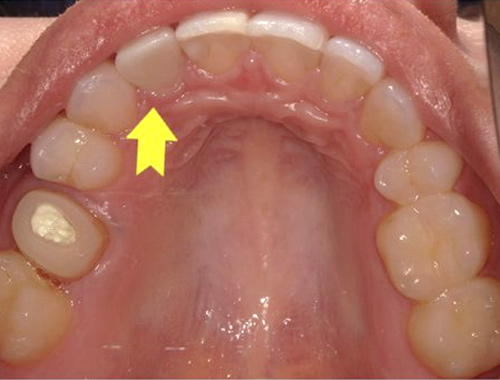

保険診療で使用されていた金属の詰め物(いわゆる銀歯)を、白くて自然な見た目のセラミック(ジルコニア)に変更した症例です。金属の詰め物は強度に優れている一方、笑ったときや口を開けたときに目立ちやすく、長い年月が経つと金属成分が溶け出して歯ぐきが黒ずんで見えることがあります。

それに対し、セラミックの詰め物は見た目がとても自然で、天然歯とほとんど見分けがつかない仕上がりが可能です。金属を一切使用しないため、金属アレルギーの心配がなく、身体にも優しい素材です。

今回使用したジルコニアは、セラミックの中でも特に強度に優れており、歯を薄く削って作製できるという利点があります。一方で、オールセラミックに比べると透明感はやや出にくい素材です。患者さまから「なるべく歯を削らず、強度も確保したい」とのご要望があったため、このジルコニア素材を選択しました。精密に作製されるため適合性にも優れており、しっかりとフィットして虫歯の再発を防ぐ効果も期待できます。

写真では、治療前後の違いをご覧いただけます。黄色い矢印の部分が、実際にセラミックに置き換えた箇所です。治療後は口元の印象が明るくなり、患者さまにも大変ご満足いただけました。

治療期間通院3回(むし歯治療、型取り、セット)、約2週間程度

費用目安税込77,000円×2